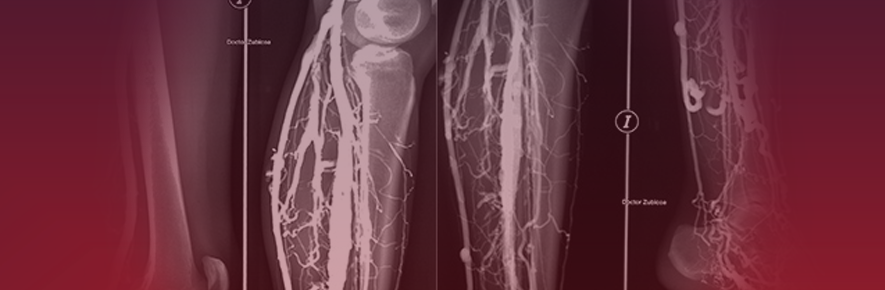

flebografia

1. consiste en la exploracion diagnostica que permite el estudio de la circulacion venosa de las extremidades

1. procedimiento en la que toma una radiografia de las venas despues de inyectarun tinte en ka medula osea o venas